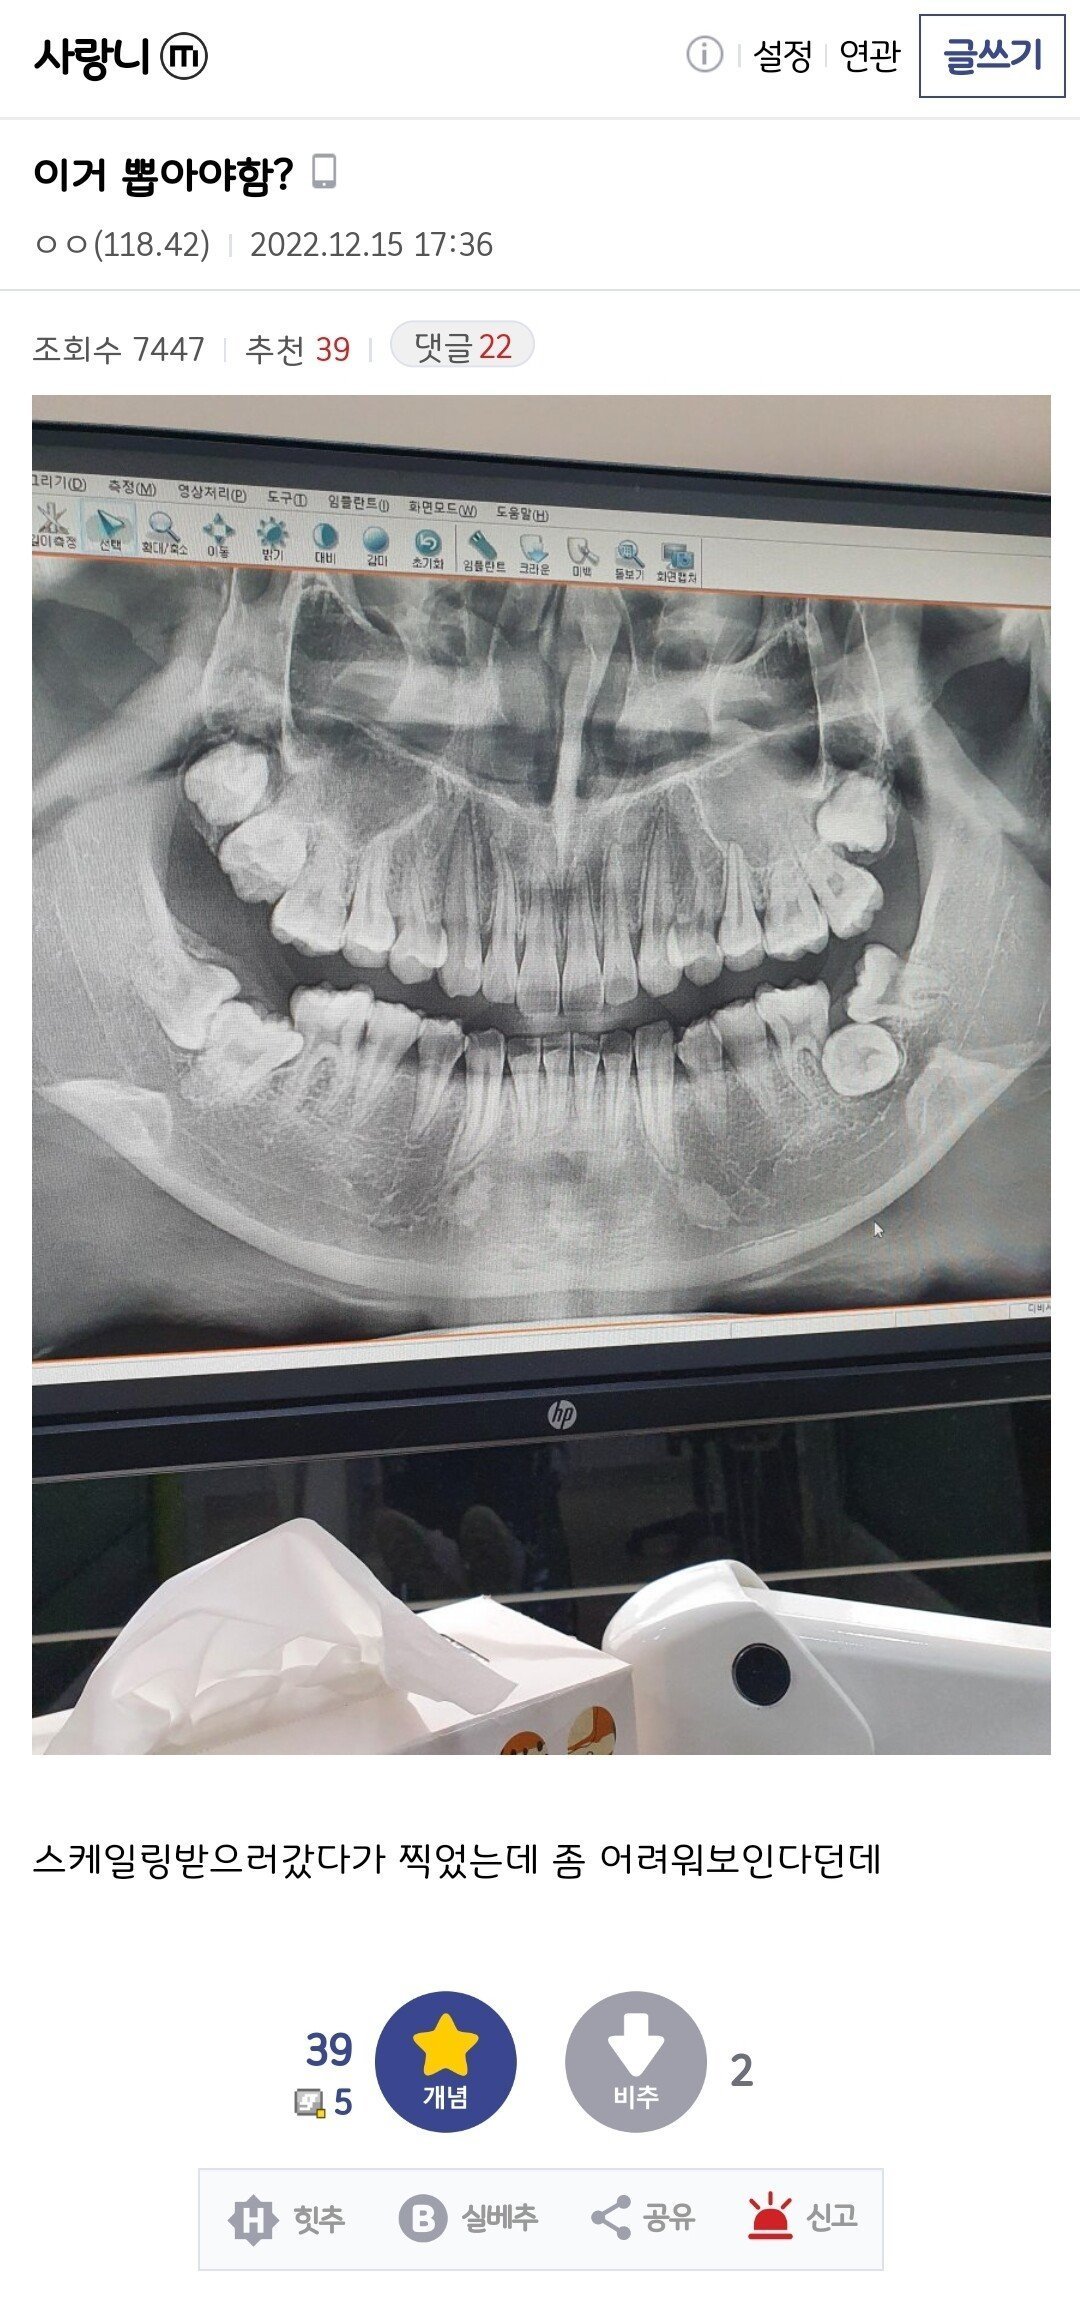

의사도 좀 어려워보인다고 말한 사랑니 수준.jpg